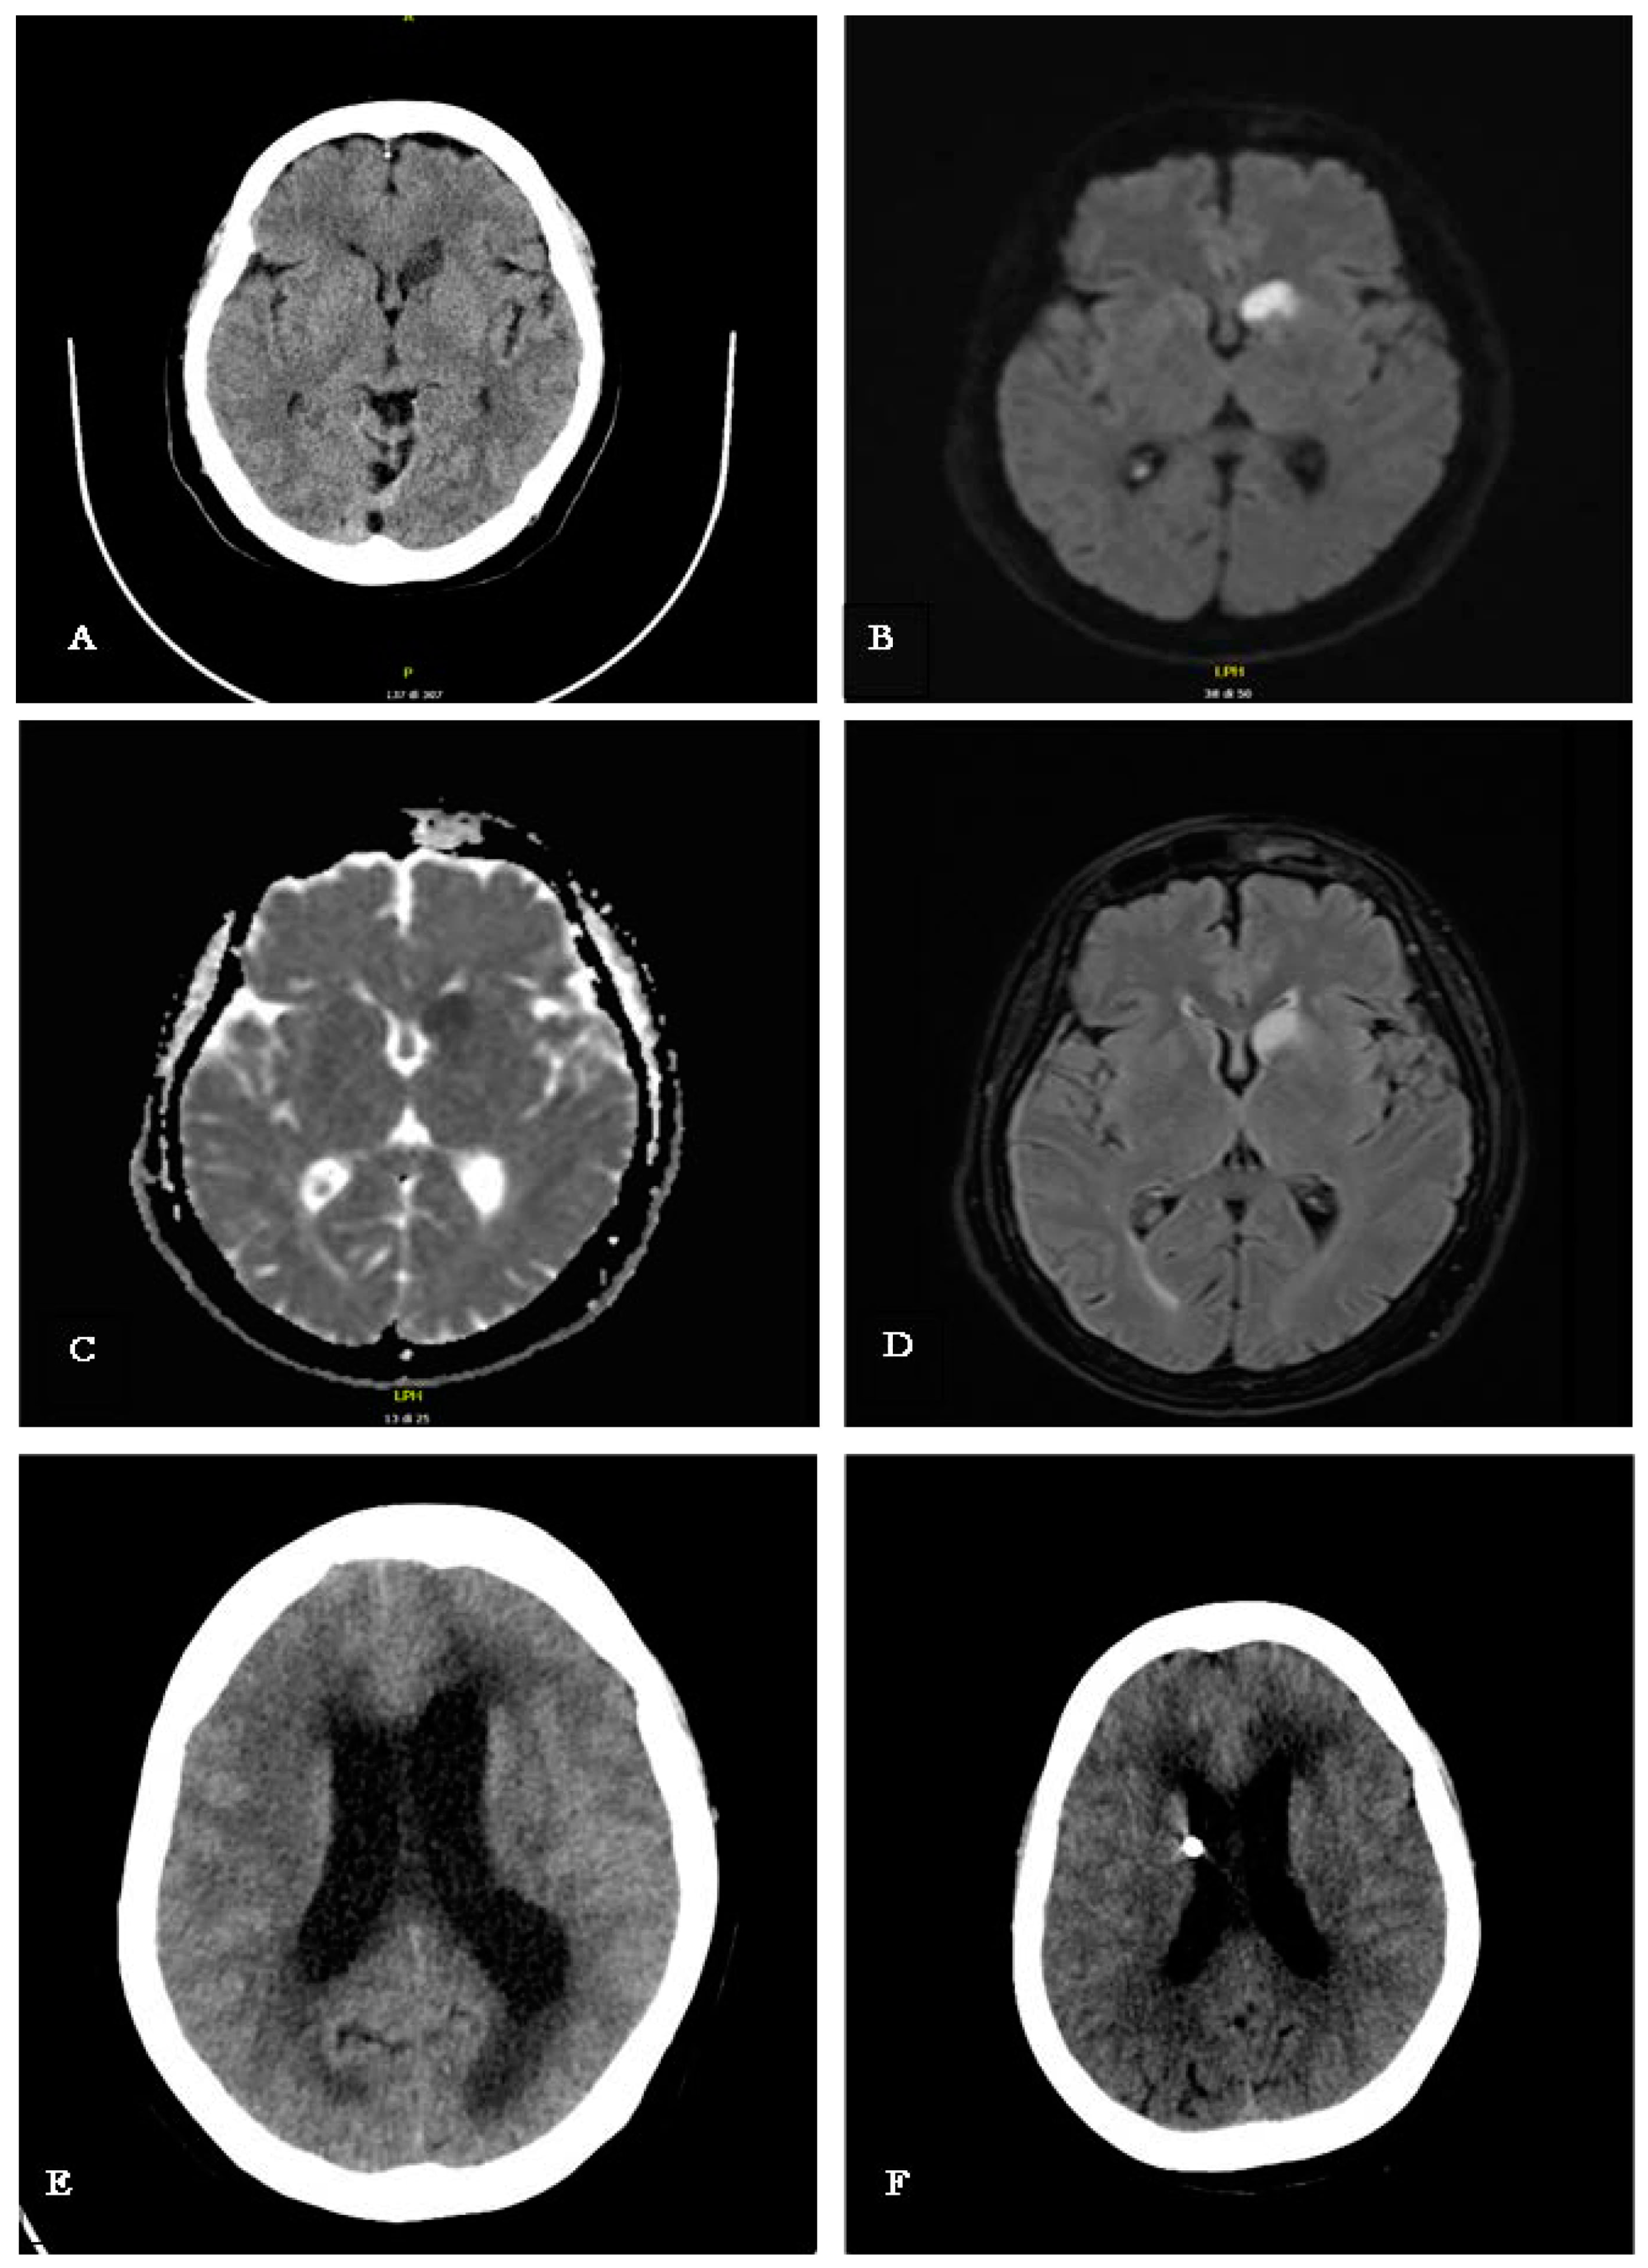

| Day 0 | Generalized weakness, fever (39 °C), persistent headache. | CT scan: Ischemic lesion in the head of the left caudate nucleus. |

| Day 7–8 | Transferred to Infectious Diseases Department. Progressive decrease in arousal, leading to coma. | CT scan: Acute hydrocephalus detected. Neurosurgery: External ventricular drain inserted urgently. |

| Day 9 | Improvement in consciousness level. Continued ideomotor slowing, apathy, and abulia. | MRI with contrast: Leptomeningeal enhancement and new ischemic lesion at left corona radiata; hydrocephalus with signs of recent transependymal resorption. |